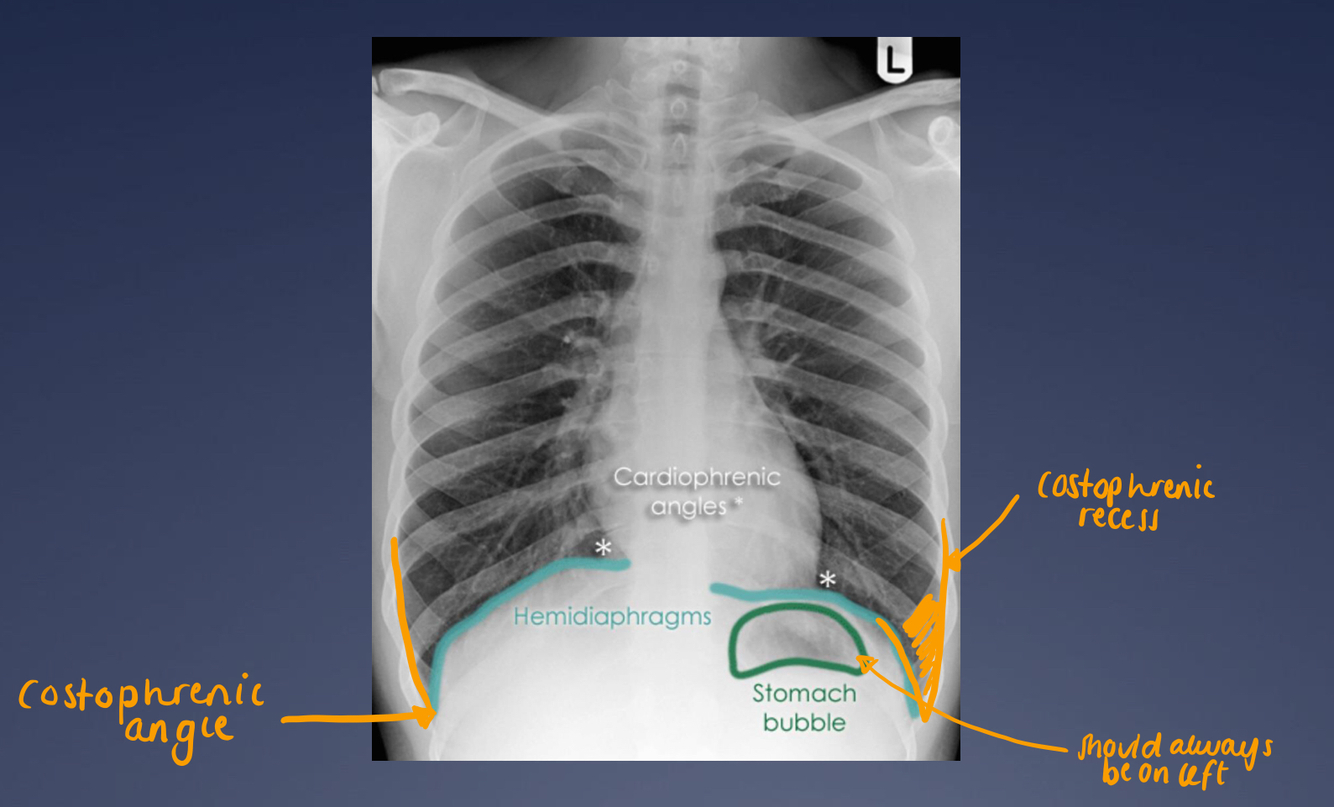

How should we see the diaphragm on an xray?

Running all the way up to the vertebral bodies